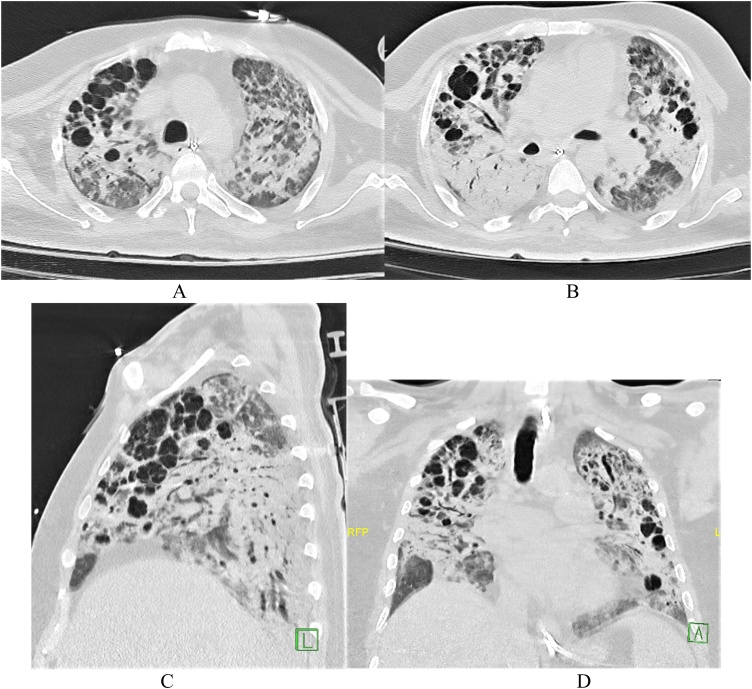

最新の疫学的調査でも、新型コロナ関連肺炎と人工呼吸器による肺障害は高い相関関係にあることが報告されています(Pulmonary barotrauma in COVID-19: A systematic review and meta-analysis. Ann Med Surg (Lond). 2022 Jan;73:103221. doi: 10.1016/j.amsu.2021.103221 )。